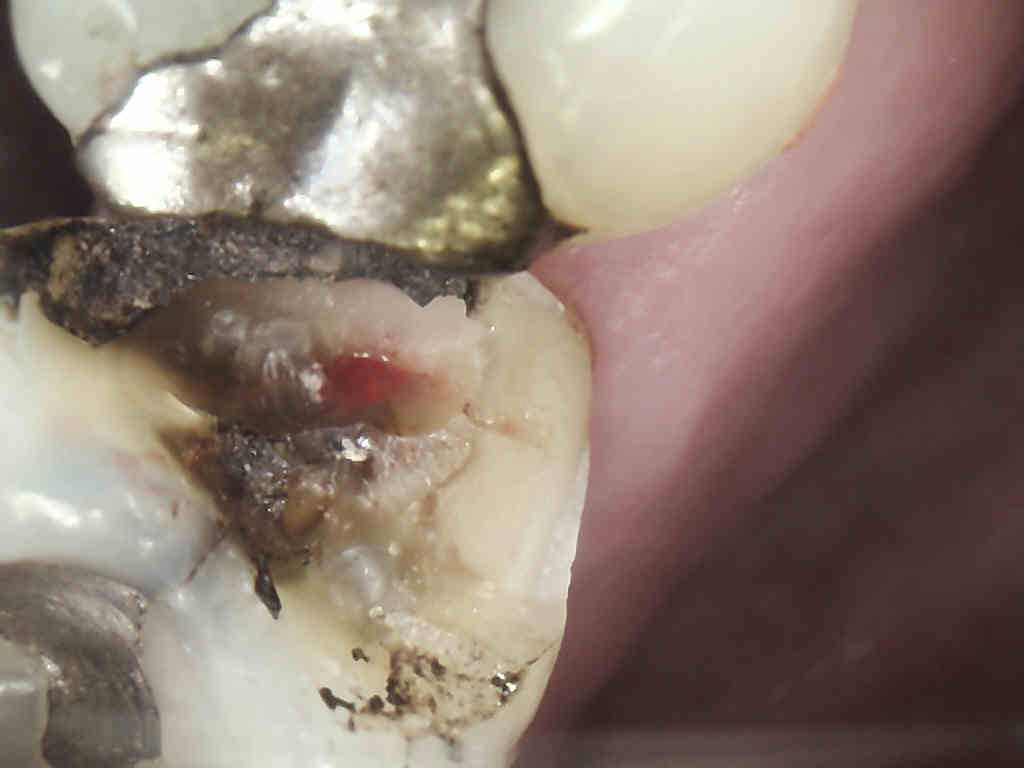

| Internal resorption |